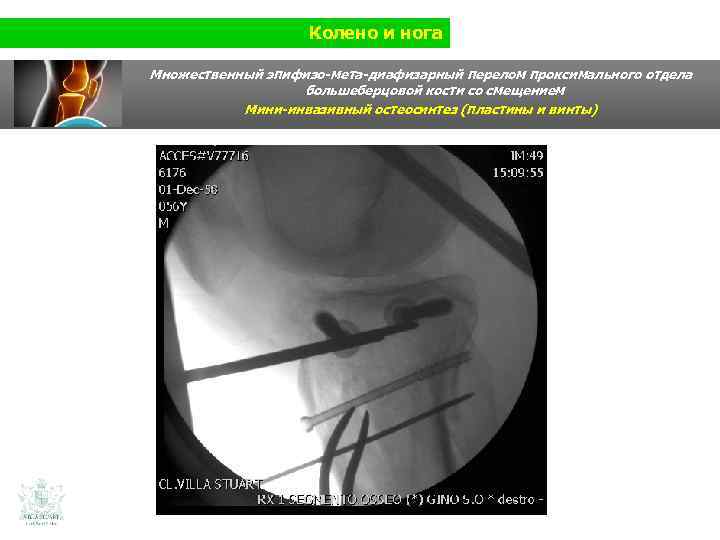

Колено и нога Множественный эпифизо-мета-диафизарный перелом проксимального отдела большеберцовой кости со смещением (Shatzer 6) Мини-инвазивный остеосинтез ( пластины и винты)

Колено и нога Множественный эпифизо-мета-диафизарный перелом проксимального отдела большеберцовой кости со смещением Мини-инвазивный остеосинтез ( пластины и винты)